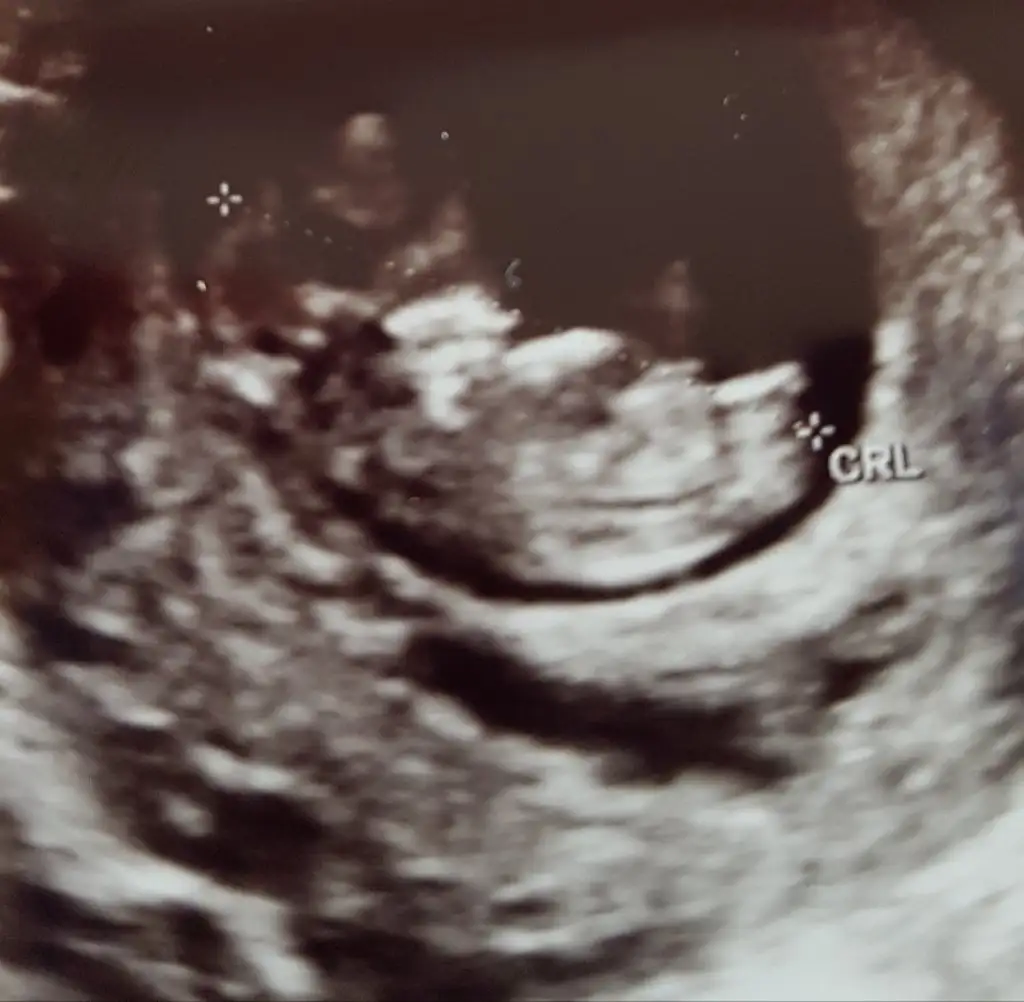

Kız sanki başka usg varmı 11+ yada 12+ olmalı100 de 100 kızım diye bağırıyor dimi kizlar:) yanılıyor muyum?11+1

Çelişkide mi kaldınız? Sizin yorumunuz benim için önemli.. Yok başka fotosu bi bu var. Zaten daha12 haftalık olmadiKız sanki başka usg varmı 11+ yada 12+ olmalı

Şimdilik kız diyorumÇelişkide mi kaldınız? Sizin yorumunuz benim için önemli.. Yok başka fotosu bi bu var. Zaten daha12 haftalık olmadi

Teşekkür ederim . İkisi de miKız bence

Altta ki erkek sankiTeşekkür ederim . İkisi de mi

Sağlıkla gelsin biri kız bi erkek diyorum